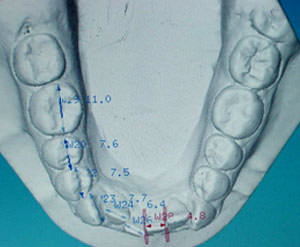

Arco inferior

Fig. 10

Oclusograma inferior

El análisis de Bolton es un elemento de diagnóstico que hay que tener en cuenta sobre todo si se quiere cuantificar si el problema es una discrepancia de tamaño de los dientes superiores o de los inferiores (masa dental). Para diagnosticar éste problema, se realiza una medición del ancho mesio-distal de las piezas dentales en los modelos de estudio, tanto de la arcada superior como la inferior, excepto segundos y terceros molares (12 piezas por arcada) para determinar si el problema es en la parte anterior, posterior, superior o inferior.(4,13) Es indispensable por lo tanto, el contar con modelos de estudio que nos permitan la realización de una adecuada medición. (Figs.7,8,9,10,11 y 12 )

En las fotografías laterales podemos corroborar una Clase II molar y canina de Angle derecha e izquierda, un overbite del 20%, overjet de 2 mm, apiñamiento superior de -5.5mm y un inferior de -3mm, en el análisis de Bolton presenta un exceso de 6.4mm en inferior en la suma de todas las piezas (12´s) y un exceso de 5.1mm en las piezas anteroinferiores (6´s). (Fig. 24 a 29)